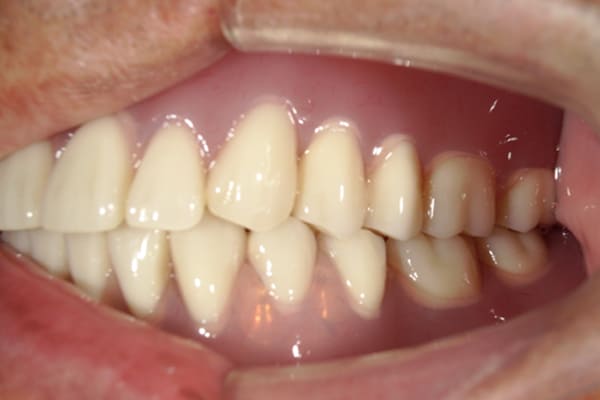

治療前後の口元の比較

こちらは、口を少し開いた時の治療前と治療後の

口元です。

正面から見た時にクラスプが目立たないように、

歯ぐきになじむ素材にて入れ歯を製作し、痛くなく自然に馴染み快適に生活を送れるようになりました。